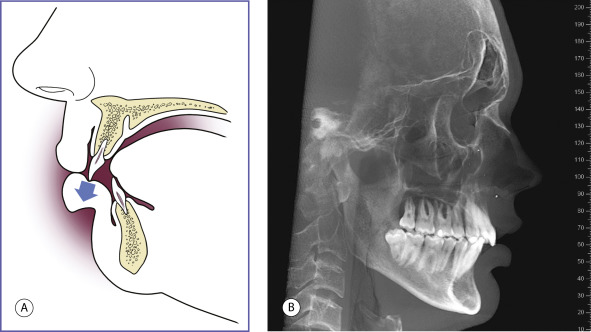

When the angle is already acute, chin augmentation will make it more acute, thereby deepening the labiomental angle. Such deepening is usually dysaesthetic. Certain patients with retrognathia have their upper central incisors abutting on their lower lip, thrusting it forward, and creating a deep sulcus ( Fig. 11.3 ). Depending on the occlusal status, these patients may be better served with repositioning of the entire mandible by sagittal split osteotomy.

Structures susceptible to iatrogenic injury during chin augmentation include the mental nerve as well as the lower lip retractors and elevators. Their anatomy is depicted in Fig. 11.8 .

The inferior alveolar nerve is a branch of the mandibular nerve (V3). It enters the mandibular canal with the inferior alveolar vessels through the mandibular foramen, which is located in the inner aspect of the ramus of the mandible. The nerve, together with vessels, courses obliquely from the ramus to the body where it exits as the mental nerve through the mental foramen, which is located at the level of the first or second premolar. Hwang et al. documented the course of the inferior alveolar nerve in Korean cadavers. They found that the foramen was located below the second premolar tooth in approximately two-thirds of the cadavers studied. Vertically, the mental foramen was located almost halfway from the tip of the alveolar process to the lower border of the mandible. They also found that the terminal mandibular canal is an average of 4.5 mm under the mental foramen, advances 5 mm anteriorly, loops, and ends at the foramen. The potential location of this nerve is important to recognize when placing screws or performing horizontal osteotomies of the mandible. Any cuts or holes made in the bone should be placed at least 6 mm beneath the foramen. After exiting the foramen, the mental nerve divides into two or three branches to supply sensation to the mucosa and the skin of the lower lip and chin.

The inferior alveolar nerve courses at a level inferior to the mental foramen.